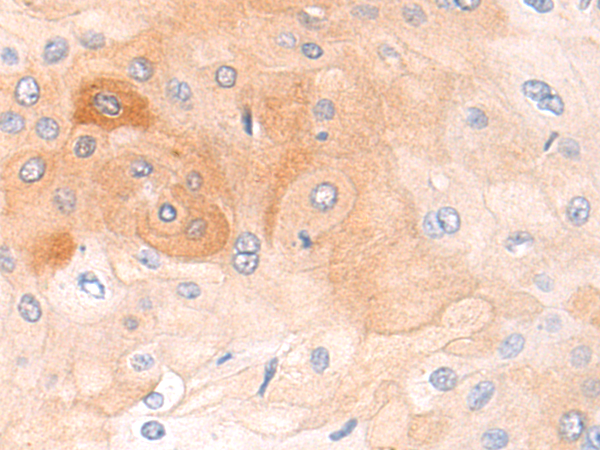

分类: 科研抗体货号: P04734别名: GVI; PLA2; INAD1; NBIA2; iPLA2; NBIA2A; NBIA2B; PARK14; PNPLA9; CaI-PLA2; IPLA2-VIA; iPLA2beta应用: IHC反应种属: Human, Mouse, Rat